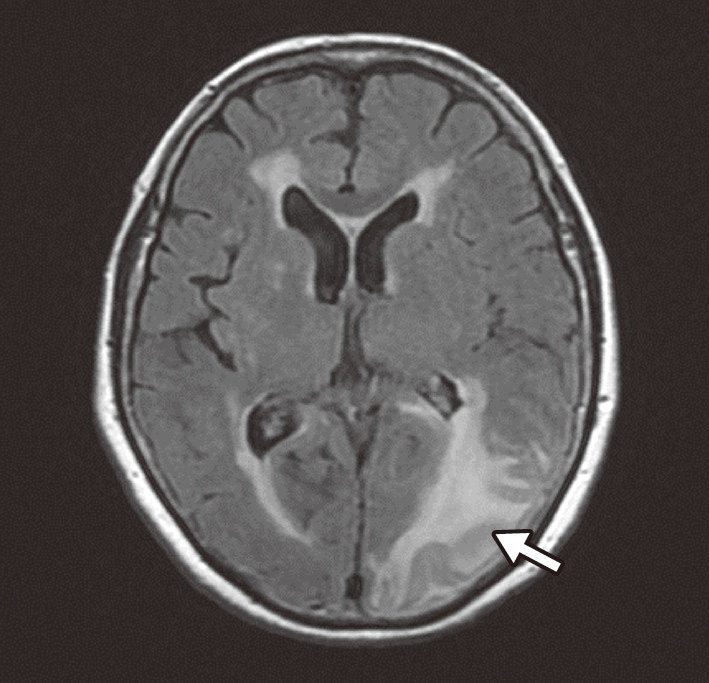

ⓔ図18-5-14 脳アミロイドアンギオパチー関連炎症のMR像